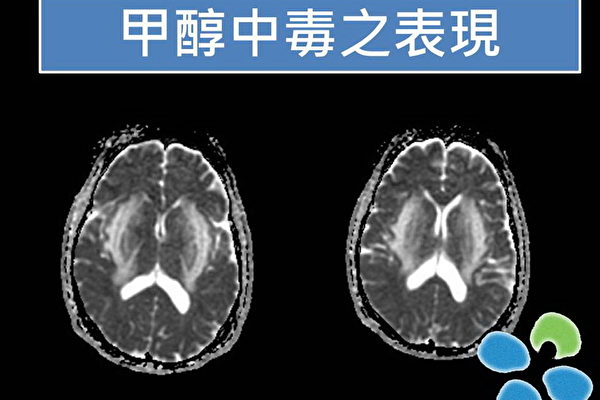

Medical tests revealed an abnormal indicator. In the afternoon of the same day, another worker who dined with them also showed the same abnormal indicator. Upon seeing the two cases, doctors suspected methanol poisoning.

Examination results showed that Li’s blood methanol level on November 25 was still as high as 41.33 mmol/L, while the normal value should be less than 0.0156.